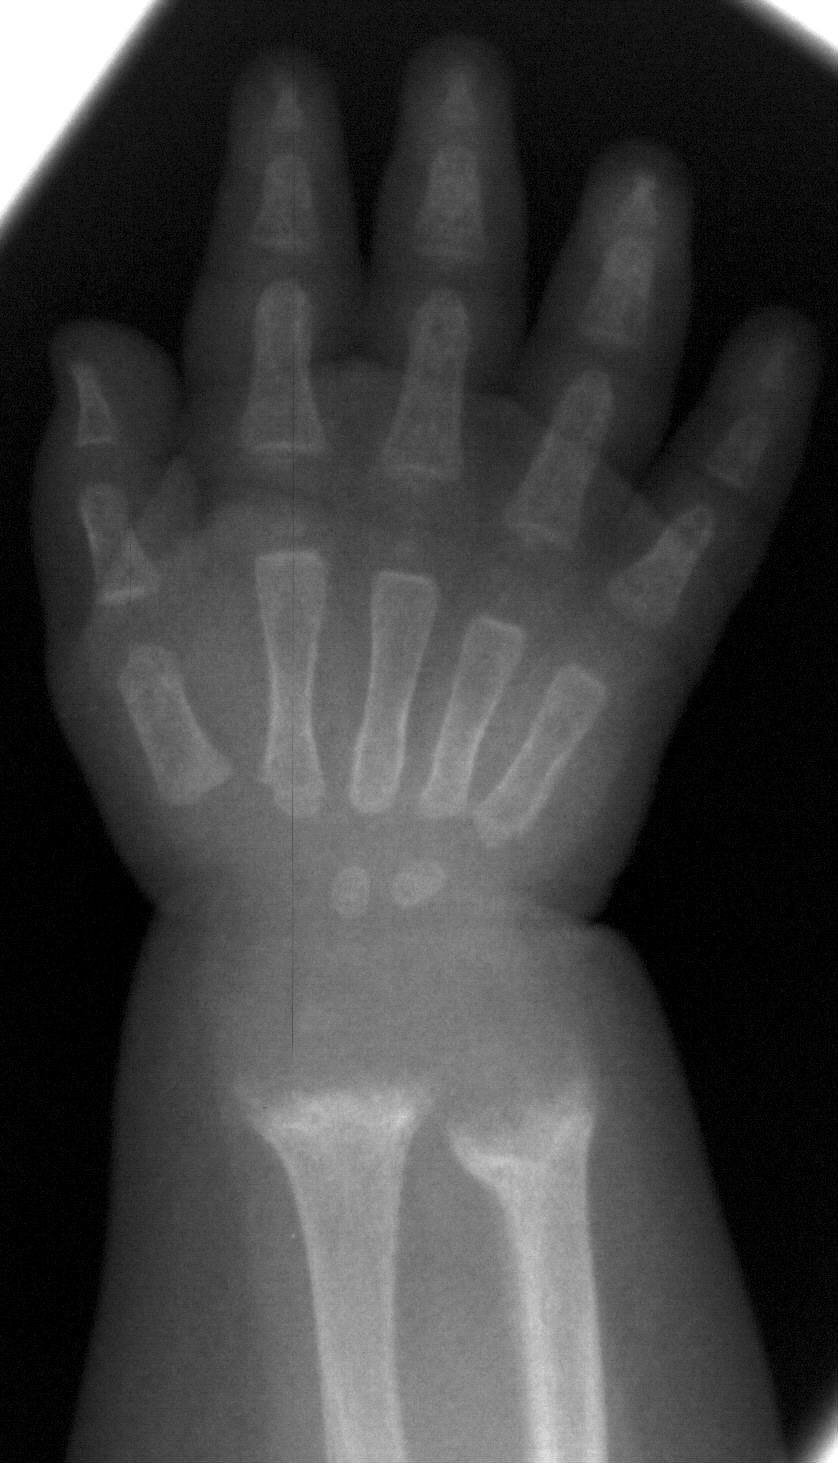

Rachitis. Rachitis can be caused by insufficient vitamin D alimentation, a decrease in mineral uptake (e.g.: premature infants) and vitamin D shortage due to malabsorption (coeliakia, cystic fibrosis) or a disorder in vitamin D production process. Its clinical symptoms are very characteristic: the wrist is swollen, a palpable mass or strain is often found on the anterior ach of the ribs, the skull is compressible like a ping-pong ball. X-ray examination: the typical signs of rachitis can always be found in the transitional ossification zone. On wrist radiograph the distal metaphysis of the ulna and the radius have an irregular contour, they are hollowed, the distance between the bone and the epiphyseal core is widened.

Image

40. Wrist X-ray. The distance of the wrist bones and radial/ulnar epiphysis is widened, uneven and hollowed, at parts the bone density is decreased. Rachitis